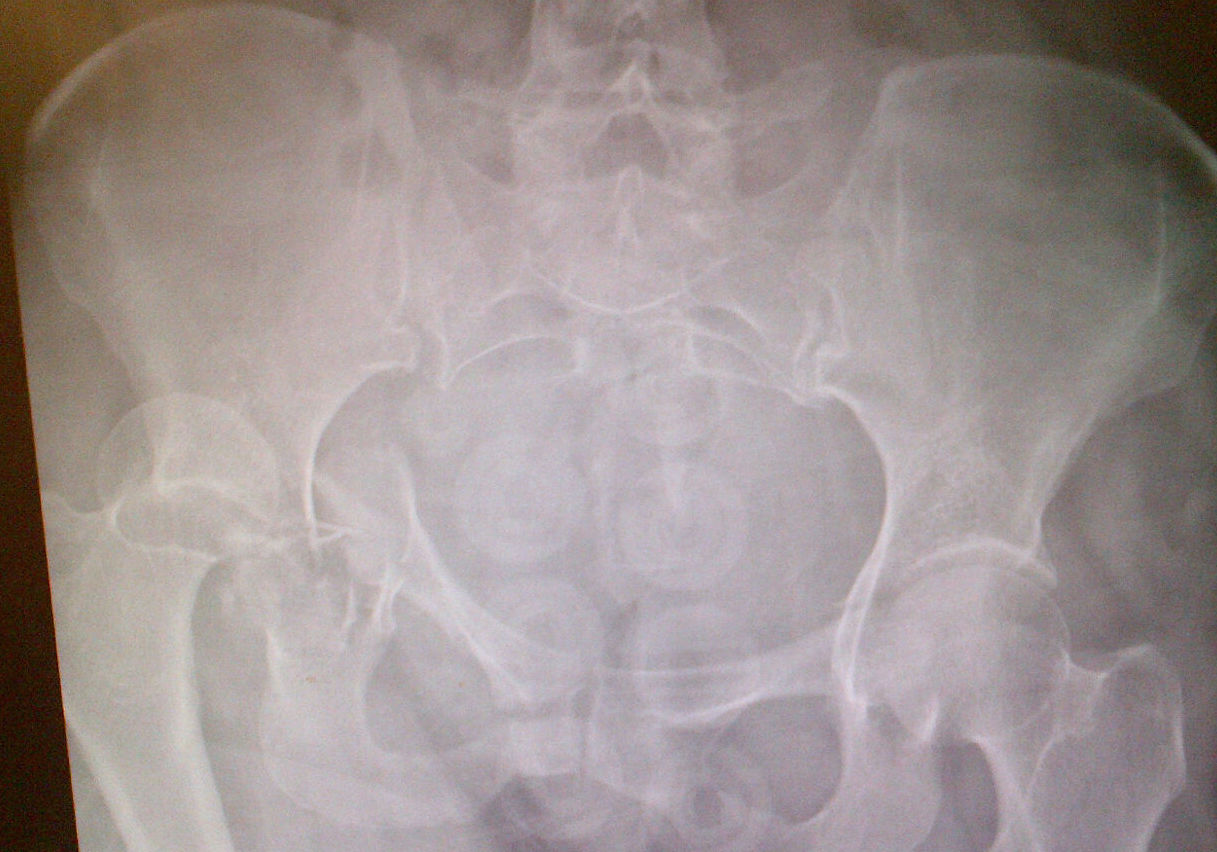

Clinical Features / Xray

Posterior dislocation

- leg shortened, flexed, adducted & internally rotated

- head small on xray

Anterior dislocation

- leg short and externally rotated

- head larger on xray

Check NV status / sciatic nerve